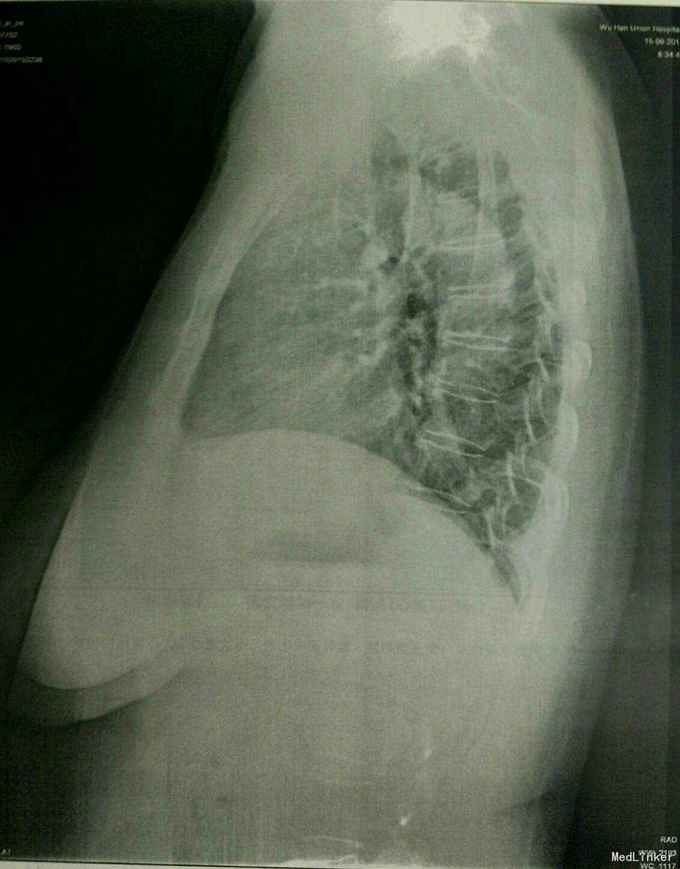

查体:T:36.5℃,P:82次/分,R:20次/分,BP:122/73mmHg。神志清楚,查体合作,面容正常,全身浅表淋巴结无肿大。心率82次/分,律齐,心音正常,各瓣膜区未闻及杂音。肺部心间波动正常,压痛及反跳痛阴性,无异常隆起及凹陷。双肺呼吸音清,未闻及干湿罗音及胸膜摩擦音。腹部外形正常,全腹柔软,未及包块,肝脾肋下未触及。双下肢无水肿。生理反射存在,病理反射未引出。 专科情况:右侧耳廓前下方见一手术疤痕,右侧外耳道口有一肿物堵塞,不能窥及鼓膜,外耳道口处有渗血。 辅检:门诊CT示:1、右外耳道口软组织稍显增厚,2、双侧中耳及内耳未见明显异常。术前常规检查未见异常。余见下图。